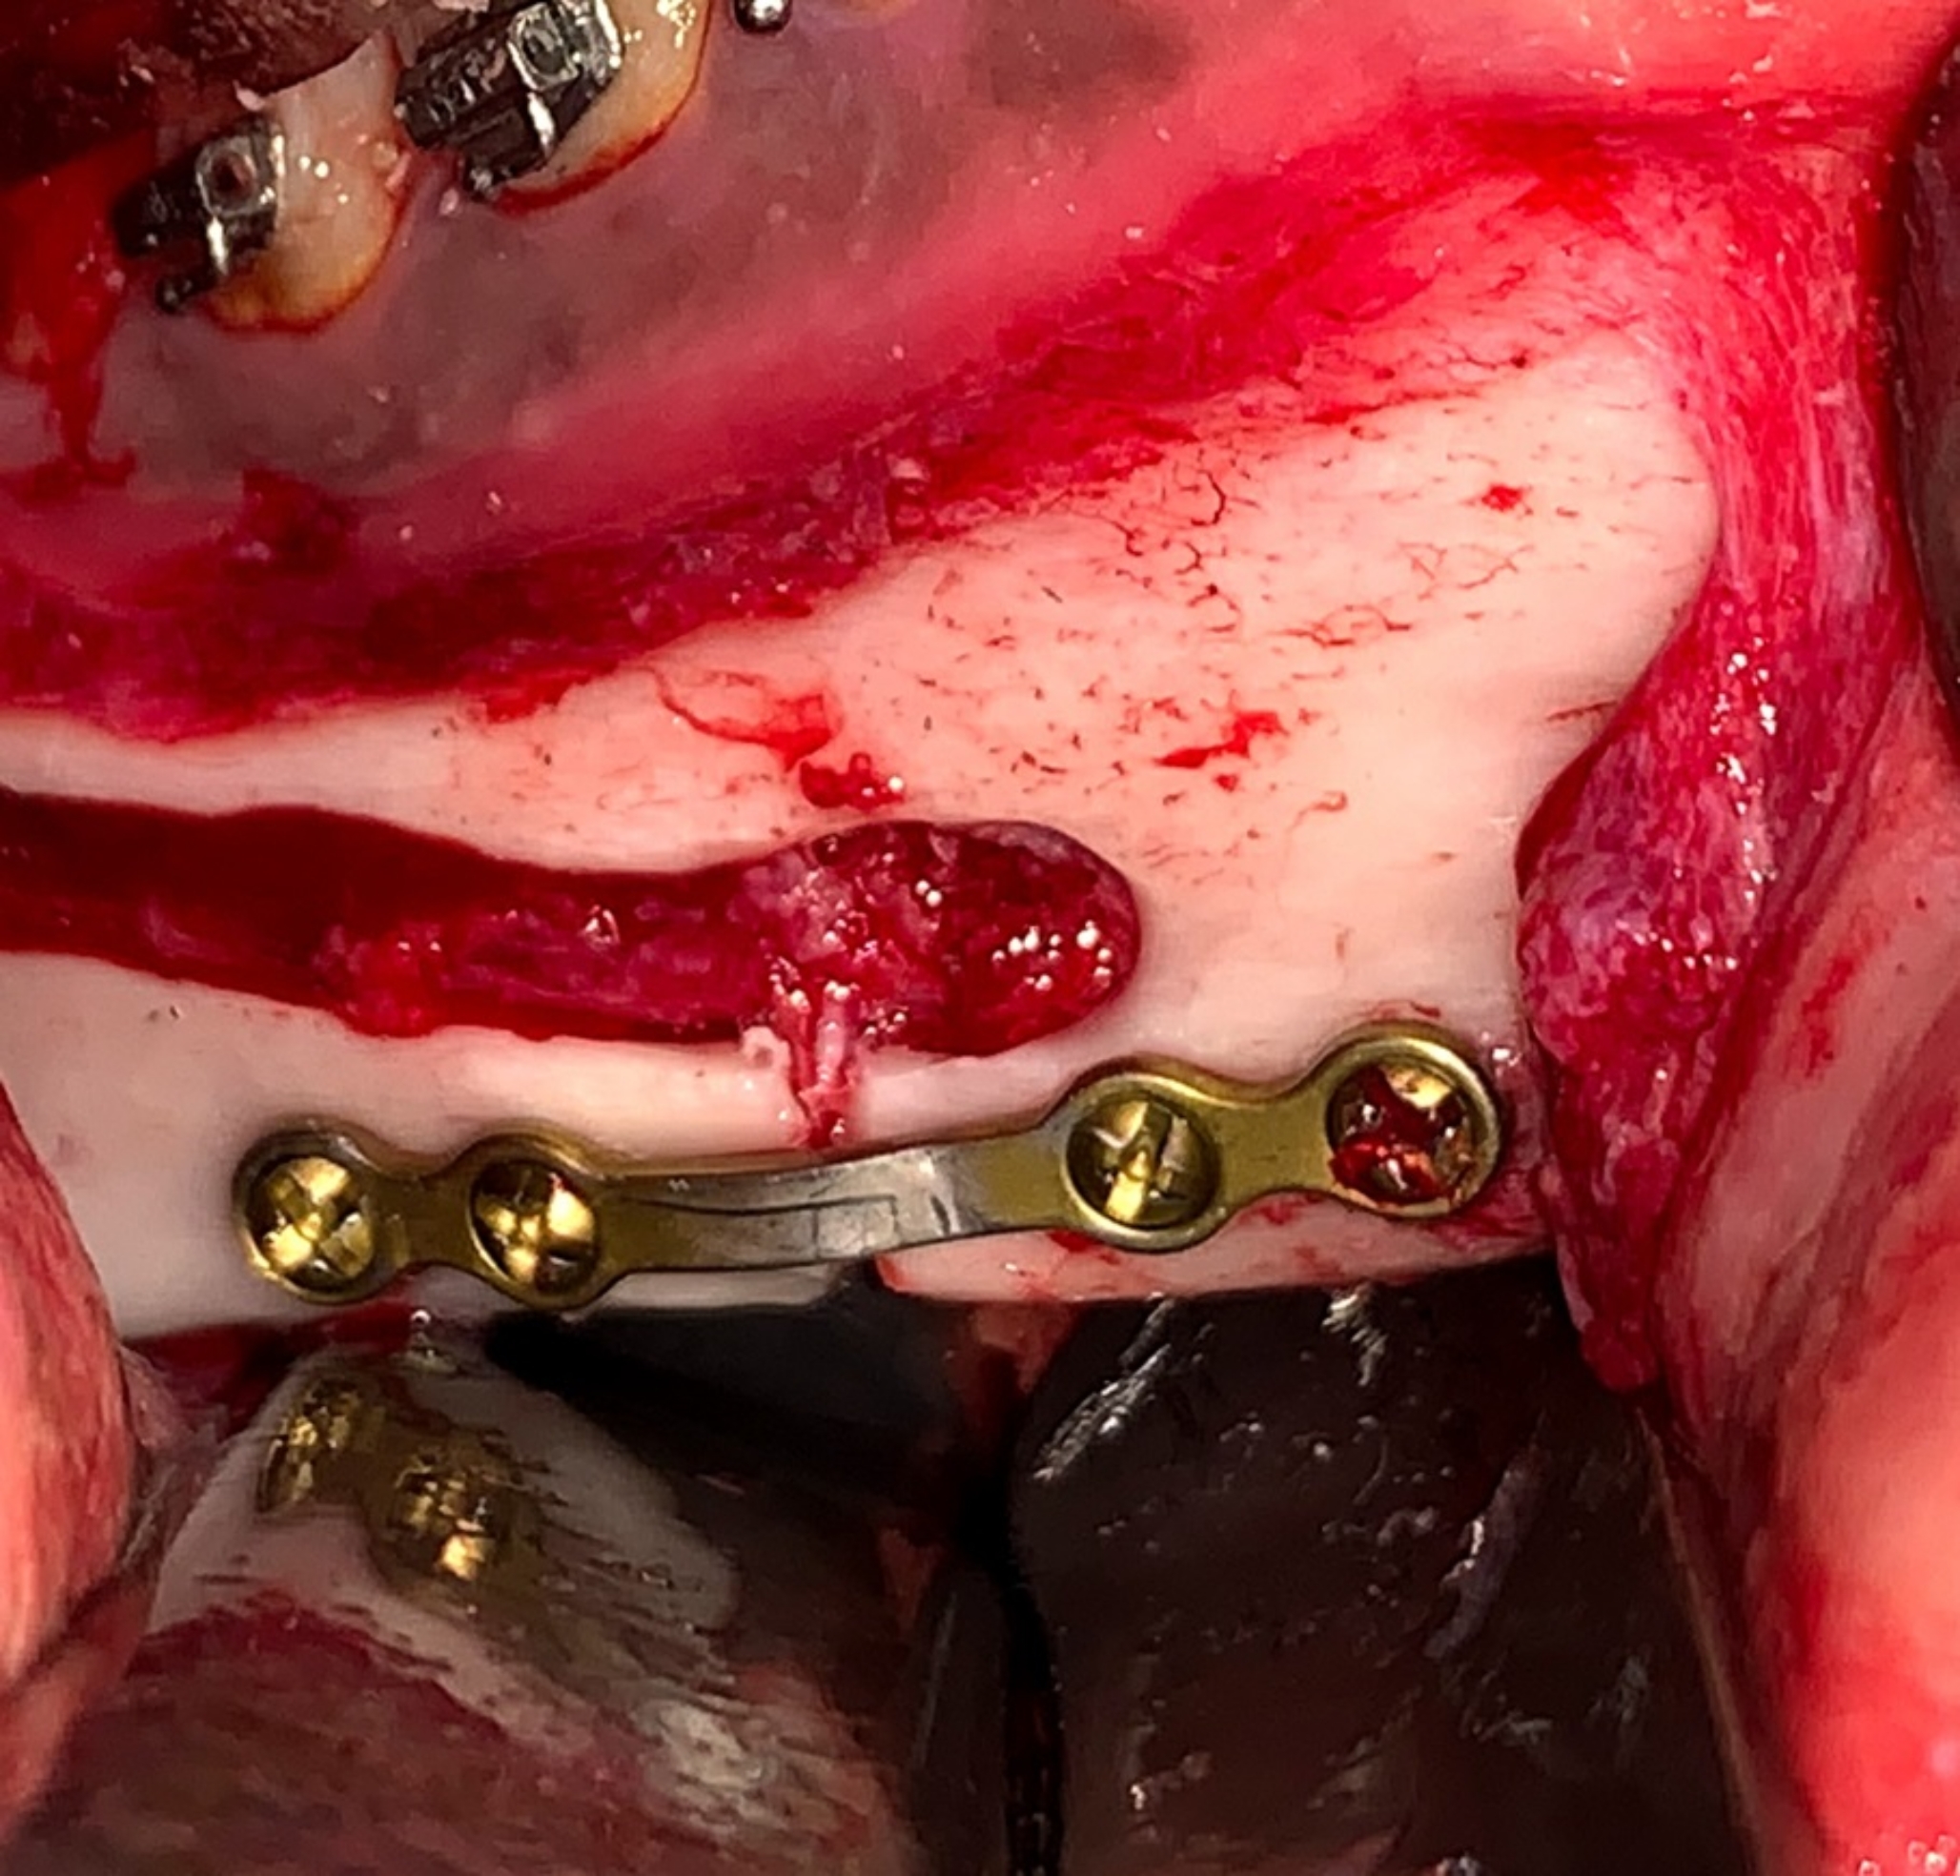

Fig. 7

Intraoperative photograph showing: Mandibular setback and pre-bent plate osteosynthesis

Based on the preoperative clinical and radiographic assessment and virtual planning enrolled skeletal class III patients were categorized in to patients requiring mono-maxillary or bimaxillary surgical intervention. The surgical procedure was performed under general anesthesia. In Bi-maxillary cases, the maxillary surgery was performed first, segment was mobilized and positioned using a cutting and drilling surgical guide associated with pre-bent plates osteosynthesis, then the mandibular surgery was performed. The mandibular surgery starts with bilateral intraoral mandibular incisions. The surgical guide was placed in position (Fig. 4). Screw holes and osteotomy lines were performed. A reference marking points were performed using a surgical fissure bur through the nerve tracing central trough of the surgical guide to mark the nerve pathway (Fig. 5). The device was removed, and the marked pathway was followed using a sinus lifting round stone to uncover the lateral cortical bone overlying the nerve. The nerve was then carefully repositioned in a lateral and upward direction using a nerve hook (Fig. 6). The intracanal osteotomy was completed through the uncovered mandibular canal using a reciprocating saw to connect the upward horizontal ramus cut with the two vertical inferior border cuts. The osteotomy lines were confirmed using spatula chisels then the proximal and distal segments were successfully separated. The distal interferences were removed while the IAN was safely lateralized, and the mandibular segments were repositioned guided with the pre-bent plates and screw holes (Fig. 7).